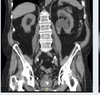

Describe what you see and what investigations would you like

CT findings post RPG reveals

Coronal image of an abdominopelvic CT With left pelcis and proximal ureter mass like filling defect